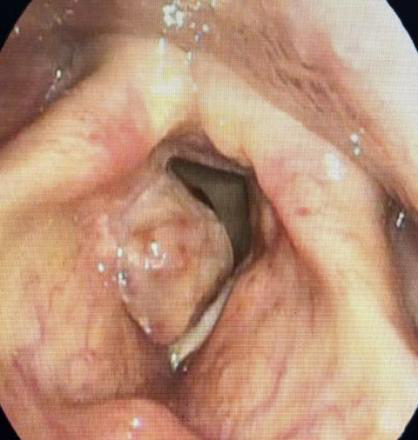

電子鼻咽喉鏡下見:右側(cè)聲帶較大腫物堵塞聲門,聲門空間很狹小。